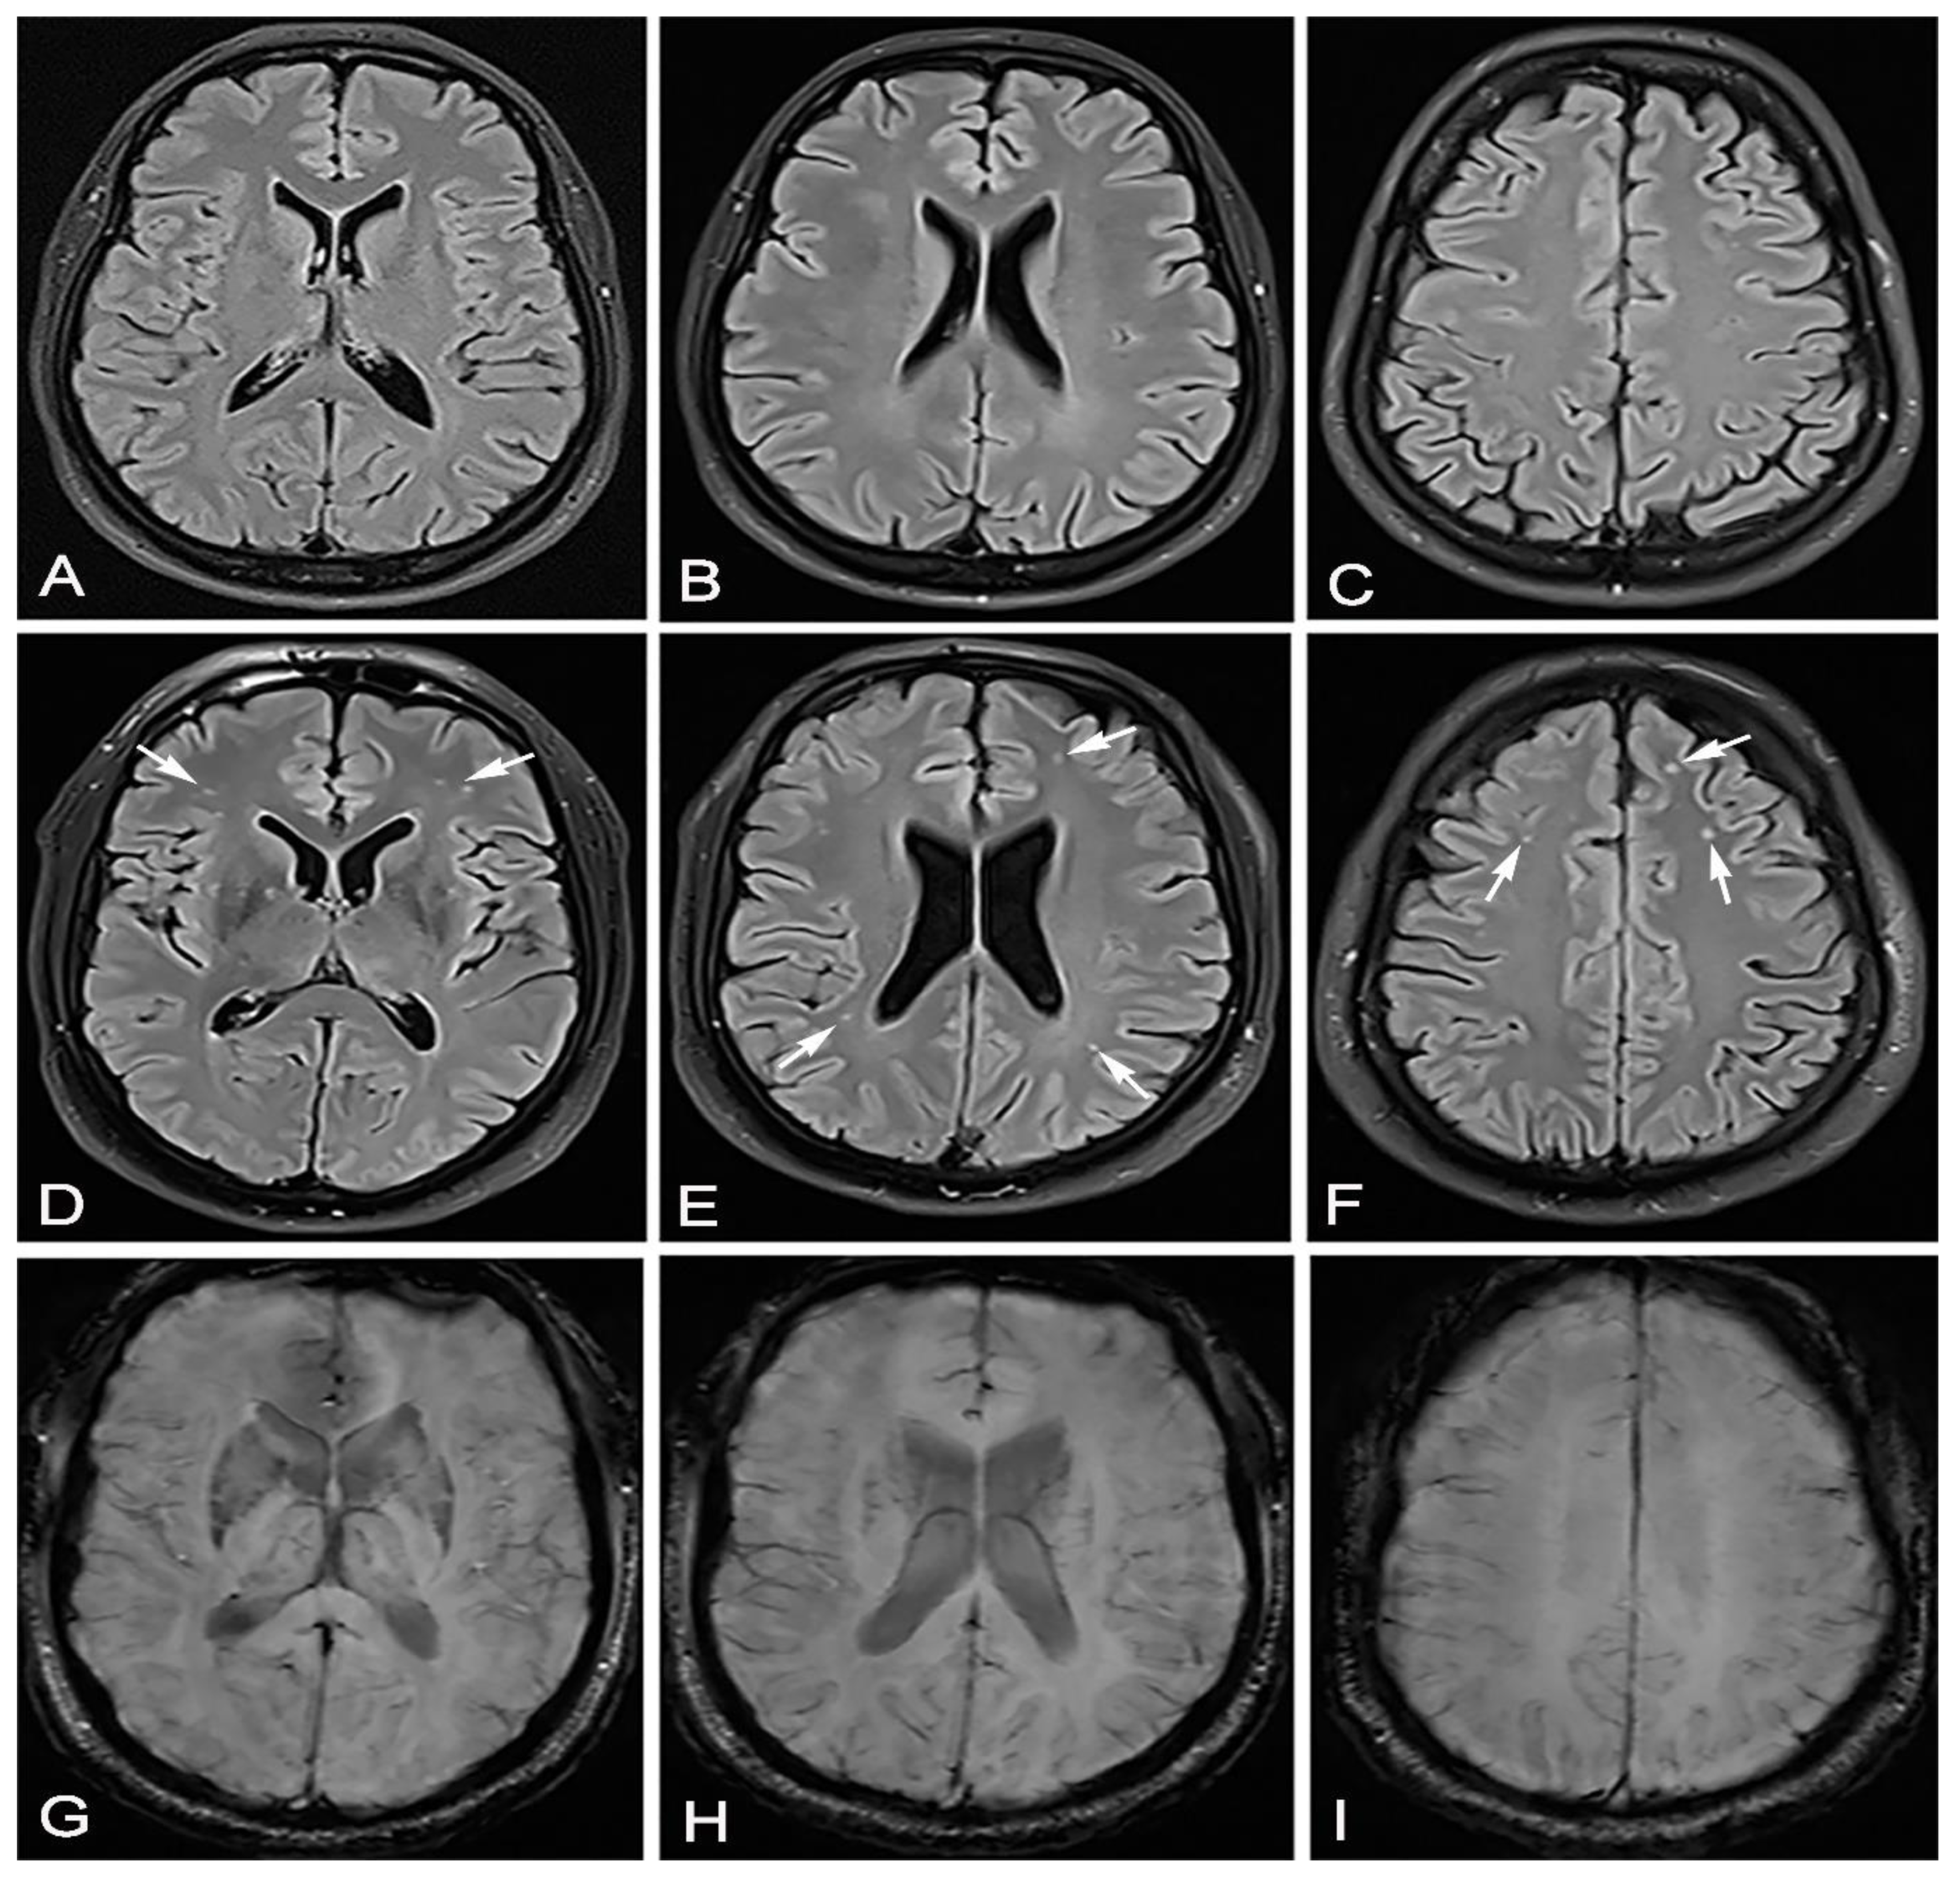

We conducted a cross-sectional observational study. We received informed consent from each participant. This study was conducted after obtaining permission from the local ethics committee. We had two groups of participants who overcame the SARS-CoV-2 infection; the diagnosis was confirmed by a positive result of a real-time reverse PCR test by nasal/pharyngeal swabs. In the first group of 16 participants, there were patients who overcame a mild form of the disease, and in the second group, there were 23 patients who overcame a moderate form of the disease. All patients who had a mild form of the disease had a normal X-ray of the lung, and patients with a moderate form of the disease had unilateral or bilateral pneumonia proven by MSCT. The group that overcame unilateral or bilateral pneumonia (Figure 1, Figure 2 and Figure 3) treated with antibiotic therapy, but without corticosteroid therapy, differed from the second group of participants, who had a mild form of disease.

Figure 1. Thirty-eight-year-old male patient without any chronic diseases was admitted to the emergency department as a SARS-CoV-2 positive with high fever, cough, dyspnea and fatigue. Chest X-ray showed (A) bilaterally gentle inhomogeneous shading initial infiltrative changes. After 9 days from the onset of infection, dyspnea worsened, chest MSCT showed (B) areas of enhanced attenuation by the type of ground glass, and patchy consolidations are seen on both sides. The patient developed bilateral pneumonia. Legend: L—left side, small A letter on panel B: A—anterior, P—posterior.

Figure 2. In June 2020, this male patient—as in Figure 1—had a completely normal brain MRI after vertigo (AC). In March 2021, 53 days after recovering from moderate SARS-CoV-2 infection, the same patient came for a brain MRI due to headache, vertigo and taste and smell disorder. Brain MRI showed hyperintensive lesions on the FLAIR sequence located mostly bilaterally frontally subcortically and bilaterally periventricularly (DF) (white arrows). The same transverse cross sections of the FLAIR sequence as on (AC), without signs of microhemorrhage on the SWI sequence (GI).